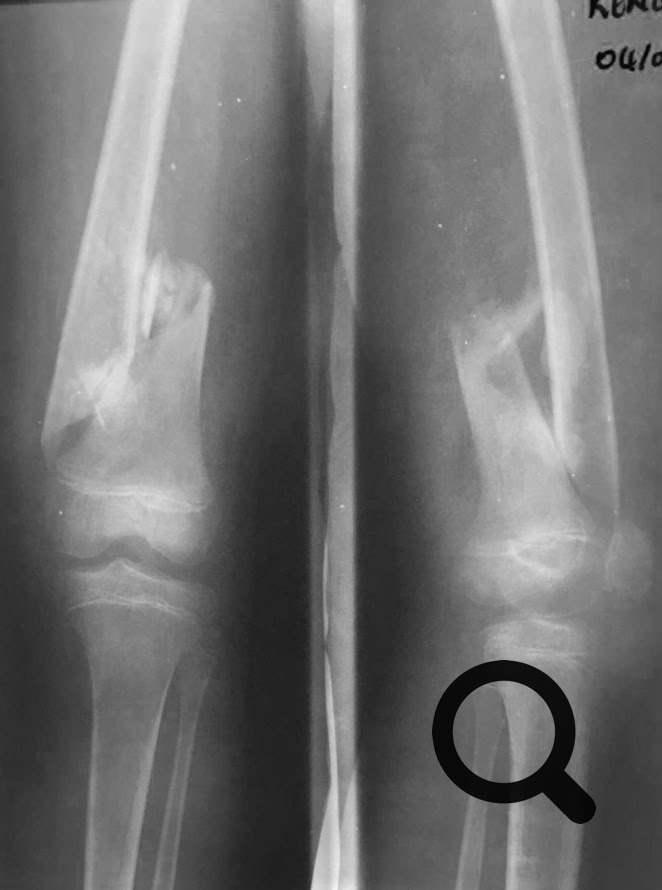

Como no podía ser de otra manera porque nos pasa siempre, nos hemos enfrentado a cirugía de alta complejidad, pseudoartrosis de húmero, fémur y tibia en adultos, así como  fracturas complejas.

Una cosa queda clara, los “masajes tradicionales cameruneses“ no son efectivos en el tratamiento de las fracturas de cualquier hueso, tanto en niños como en adultos y conducen inevitablemente a pseudoartrosis  muy difíciles de tratar.